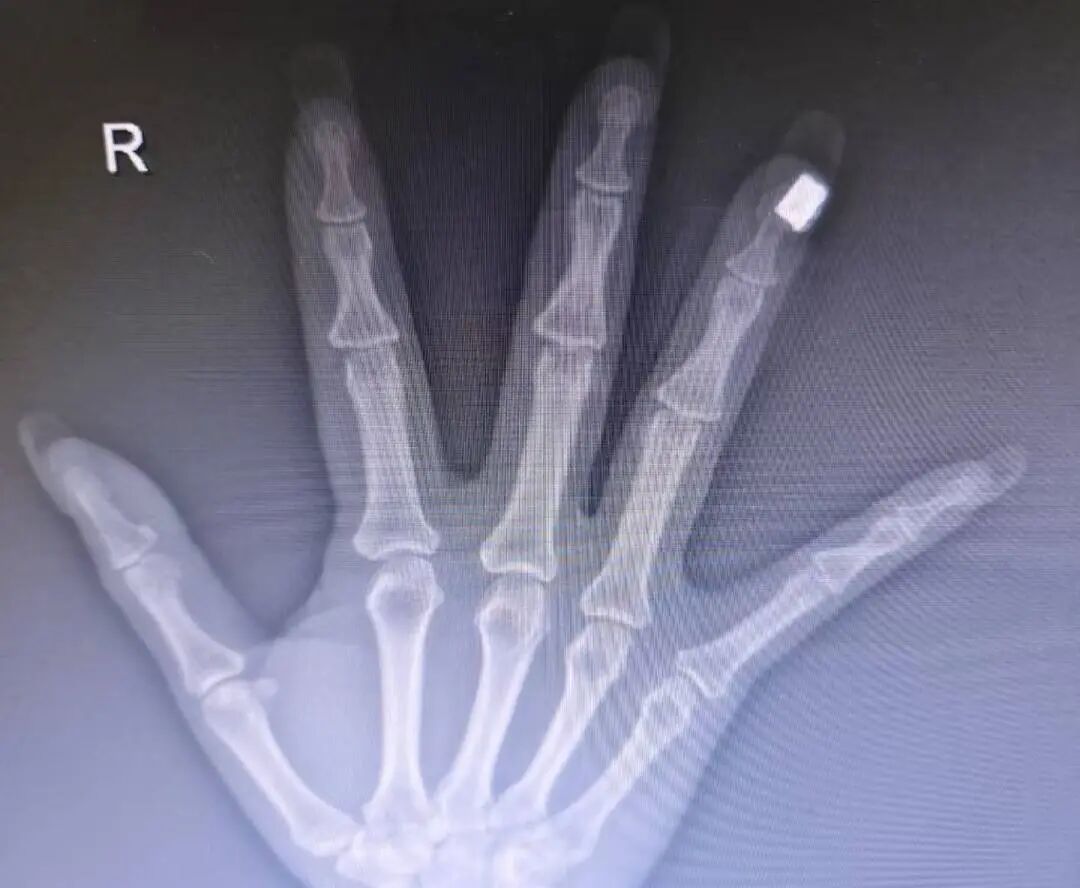

“有一次我在急诊接诊一位手外伤患者,给她拍手部X光时,意外发现美甲区域出现了高密度影,这说明美甲里面含有金属成分。”刘伟仔细观察后发现,患者的美甲上装饰有珠子或类似钻石的点缀,“外表看起来像是塑料或人造钻,但内核应该含有金属成分。”

刘伟此前遇到的案例

刘伟表示,核磁共振检查严禁携带任何金属物品。如果美甲饰品中含有铁磁性金属,在强磁场下可能被吸走,不仅可能伤及患者手指,还可能损坏昂贵的医疗设备。“问题是,很多做美甲的人可能并不清楚自己指甲上的装饰品是否含金属成分。”